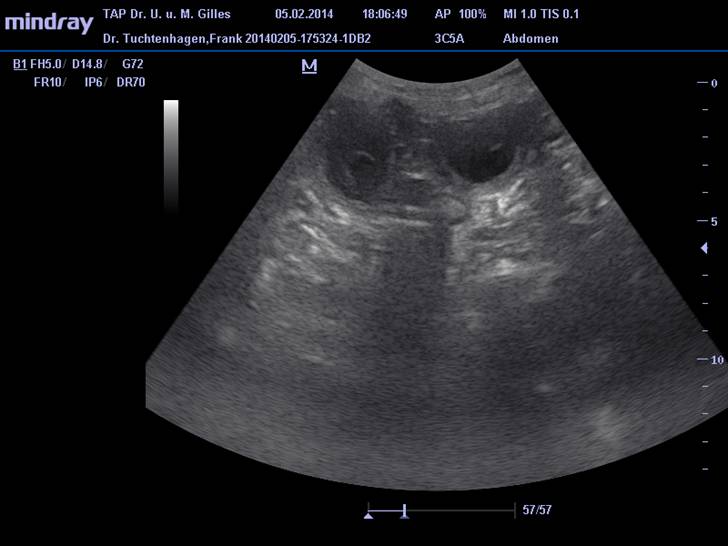

Ultraschall läßt 9 Welpen erwarten!

Endlich ist es soweit, wir haben Gewissheit: unsere Labelle ist tragend.

In der Ultraschalluntersuchung vom 5.2.2014 lassen sich die Anlagen von 9 Welpen erkennen.

Alle, soweit so früh schon beurteilbar, normal weit entwickelt.

Nächste Woche gibt's dann nochmal neue aktuelle Ultraschallbilder.